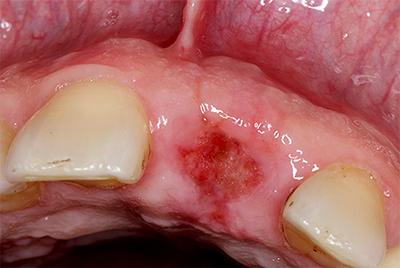

- Сухая лунка. Развивается при удалении кровяного сгустка, что грозит присоединением патогенных микробов с появлением воспалительного процесса в лунке зуба. Это требует врачебного контроля: стоматолог закроет альвеолу специальным гелем и порекомендует антибиотики.

- Альвеолит. Представляет собой опасный и сложный воспалительный процесс в лунке зуба.

- травмирование кровяного сгустка с образованием сухой лунки;

- наличие в альвеоле постороннего предмета – осколка, корня, части инструмента, ватки;

- прием горячих напитков или пищи в послеоперационный период;

- недостаточная гигиена ротовой полости.